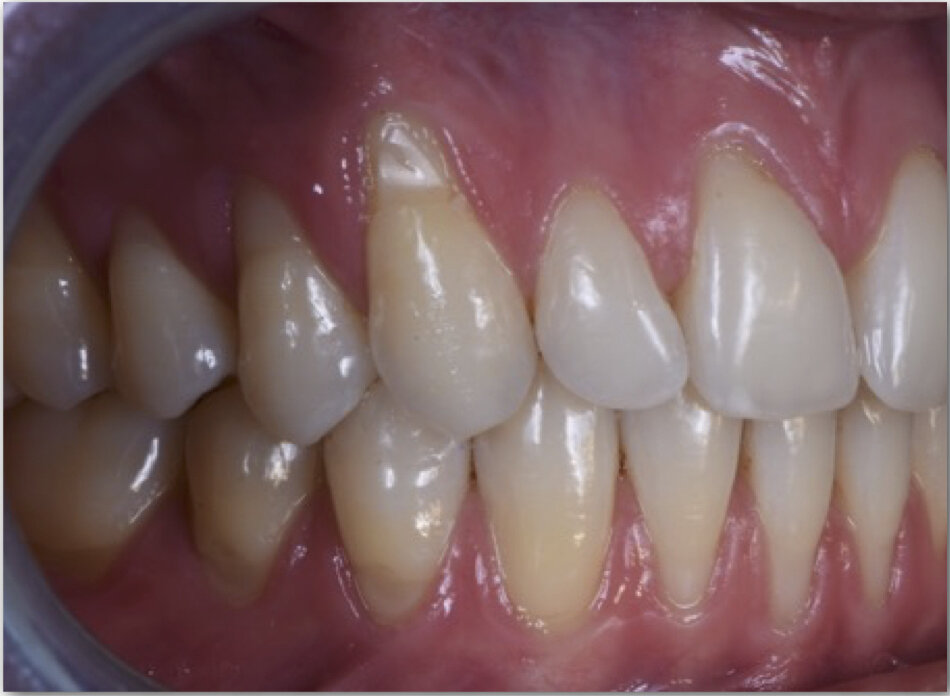

Одним из заболеваний, нарушающих розовую эстетику, является рецессия. Рецессия десны - это заболевание, в результате которого оголяется корень зуба: линия десны на верхней челюсти поднимается, на нижней - опускается.

На начальных этапах рецессия десны не сильно заметна, но с ее развитием пациенты начинают жаловаться на эстетику линии улыбки. Пожалуй, визуальная составляющая – основная причина обращения к стоматологу для процедуры закрытия рецессии.